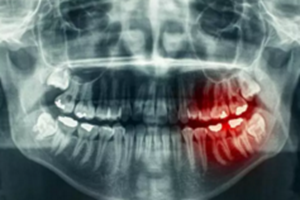

牙齒長在牙槽骨里,形態(tài)變化多端,所需要的手術(shù)時(shí)間及手術(shù)風(fēng)險(xiǎn)也有差別,所以醫(yī)生會要求拔牙前給你進(jìn)行X線牙片檢查,遇到疑難病例還要進(jìn)行牙科三維CT檢查。

為什么有些牙齒不能拔?拔牙無小事!

這些檢查手段可以讓醫(yī)生知道你牙根的長短、大小、數(shù)量、走向、彎曲程度、與周圍重要結(jié)構(gòu)的關(guān)系等等。只有明確拔牙方法,并評估拔牙風(fēng)險(xiǎn),才能使你這顆牙拔得更順暢。